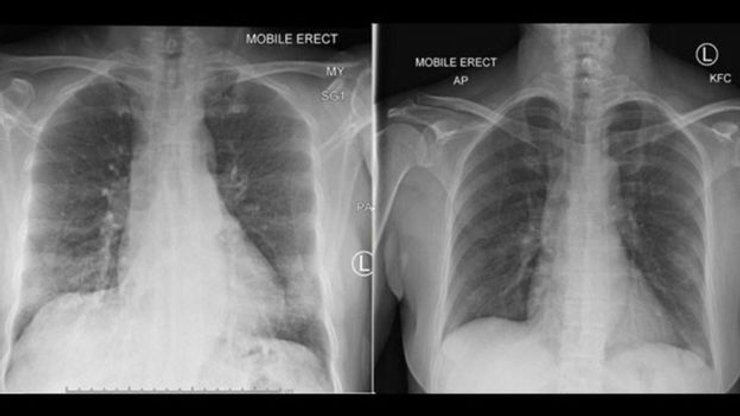

Слева на фото легкие пациента с коронавирусом, а справа показывается то, как они очищаются при выздоровлении. Фото: The Peter Doherty Institute